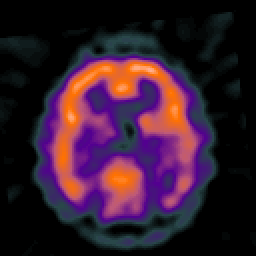

Alzheimer's disease: overlay -- Slice #34

[Home][Help][Clinical] Slice 34